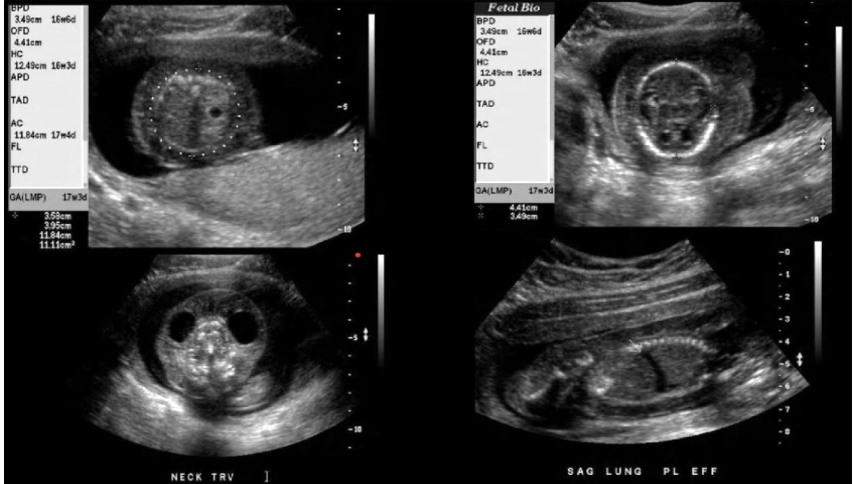

a pregnant pt w/recent acute onset of hypertension, nausea, vomit. she has no pain, cramping, or vaginal bleeding.

.

a prior US exam at 6w shows the pregnancy should now be 17w6d GA.

what maternal serum level is abn elevated

a) acetylcholinesterase

b) bHCG

c) AFP

d) inhibin A